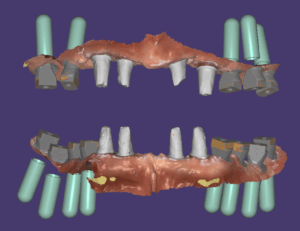

드디어 수술하는 날이 되었습니다. 보철을 제거하고 상태가 좋지 않은 치아들은 모두 제거하고 남아있는 뼈를 최대한 이용해서 뼈이식과 함께 임플란트를 식립했습니다.

위 9개, 아래 12개 식립을 했고 위에는 6개 아래는 8개에 지대주를 연결해서 수술당일 임시치아를 적용해서 즉시하중 전체임플란트 치료를 했습니다.

수술후 5개월차에 2차를 진행했습니다. 교합이 불안정해서 이 분은 스캔을 해서 맞춤지대주를 만들고 최종모양의 보철을 PMMA재료로 밀링해서 2차 당일에 끼워드렸습니다.

파워아치 전체임플란트는 올온엑스와 비슷한 고정식 전체임플란트 시스템이지만, 임플란트의 위치와 각도, 개수, 보철 설계까지 디지털 기반으로 최적화하여 전체 구조를 더 안정적으로 만드는 방식입니다. 임플란트의 생역학적 힘 분산, 보철물의 강도, 교합 설계까지 전체 아치를 하나의 시스템으로 설계하기 때문에 내구성과 안정성 면에서는 세 가지 중 가장 우수한 방식입니다. 환자 상태에 따라 임플란트 개수를 더 늘려 힘을 더 넓게 분산시키는 것도 가능합니다.